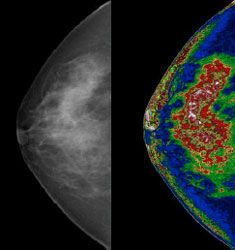

Mammogram image before MED-SEG processing, left, and afterward, right.

The program’s ability to accurately distinguish among different geological features, even those of almost identical coloring, suggested a program that could also extract huge amounts of data from the indistinct silver monotone of a typical mammogram.

Much remains to be finished, particularly software for 3D images, but Bartron has won its first commercial victory. In July, the FDA approved the company’s application to market MED-SEG™ for storing medical images for hospitals and other clients. Now Barton can earn revenue while it runs the tests needed to see whether its technology advances doctors’ ability to read mammograms and other images.

“It will probably take me 2 years to complete the tests that will demonstrate this to the FDA’s satisfaction, but from what I’ve seen, I believe this technology will improve radiologist interpretive skill anywhere from 27% to 67%,” said Walker, who is working with researchers at the University of Connecticut on diagnostic testing. “Machines can simply analyze these images in ways that human eyes cannot.”